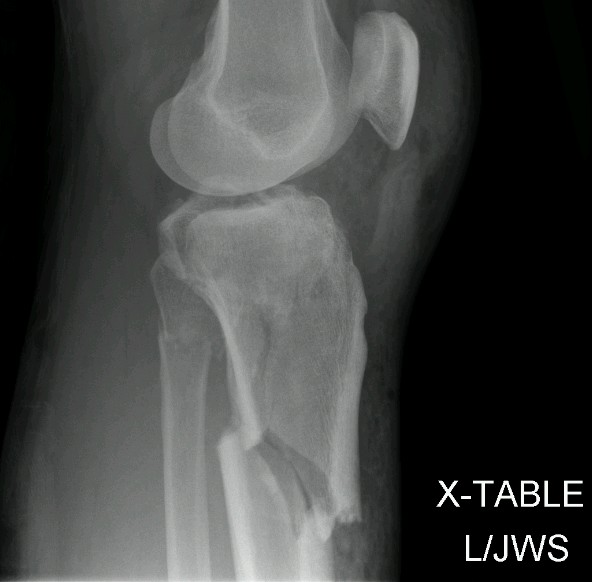

That's the external fixator they used to stabilize my knee before surgery (the swelling took 4 days to go down before they could do surgery). In case you're wondering, it's bolted into the bones in my thigh and lower leg.

Left Knee Before...